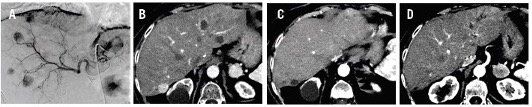

Figure 2 Liver DSA. Multiple hypervascular bilobar nodules are visualized. Post surgical hepatic artery loop (arrow). (A) Arterial phase CT scan after left lobe DEB-TACE shows hypodense residual tumors (arrows) with no enhancement. A viable right lobe lesion (arrowhead) and left adrenal metastasis (*) are noticed. (B) Follow up CT scan after right lobe DEB-TACE and sorafenib therapy onset. Right lobe HCC nodule shows complete response (arrow). Adrenal metastasis diameter remained unmodified with slightly decreased enhancement (*). Mild dilation of left bile ducts is present, probably due to post TACE ischemia (arrow). (C) and (D)

Our patient can be categorized as having a late recurrence of HCC. She was approached with a combination of locoregional treatments (as she presented with predominantly unresectable liver disease) and systemic treatment because of extrahepatic spread. Two cycles of lobar doxorubicin-loaded DEB-TACE were performed within a 2-month interval; the super-selective left TACE was technically challenging because of a postsurgical loop in the hepatic artery, making microcatheter navigation difficult (Figure 2). A complete response (per mRECIST criteria) in all liver nodules was achieved. Sorafenib was started (and reduce to 400 mg daily because of adverse events) and the last follow-up CT scan (6 months after recurrence) showed stable adrenal disease and no further sites of recurrence. At 4 years and 4 months following OLT, the patient’s performance status and liver functions are optimal. Although there is a good response to combined treatment with the radiologic assessment, AFP levels are increasing. The patient will continue sorafenib; TACE will be reconsidered in the case of intrahepatic disease. The current immunosuppression regime scheme is CNI based; a shift to an mTOR inhibitor will be considered depending on the patient’s tolerance to combination treatment (sorafenib plus mTOR inhibitor).